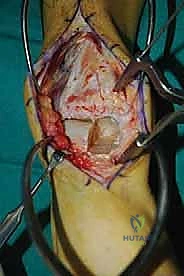

الغوص العميق في جراحة الطعم الخيفي الهيكلي (Structural Allograft Reconstruction)

يهدف هذا الإجراء العبقري إلى استبدال الغضروف والعظم التالفين والميتين بنسيج سليم تماماً مأخوذ من متبرع متوفى (طعم خيفي - Allograft). هذا الطعم يتم تعقيمه وحفظه في بنوك الأنسجة العالمية وفقاً لأعلى المعايير الطبية الصارمة لضمان خلوه من أي أمراض معدية والحفاظ على حيوية الخلايا الغضروفية.

- الترميم التشريحي الحقيقي: يسمح باستعادة الشكل الهندسي الدقيق لعظم الكاحل، بما في ذلك المنحنيات المعقدة لكتف التالوس.

- توفير غضروف طبيعي (Hyaline Cartilage): الغضروف المزروع هو غضروف زجاجي طبيعي،